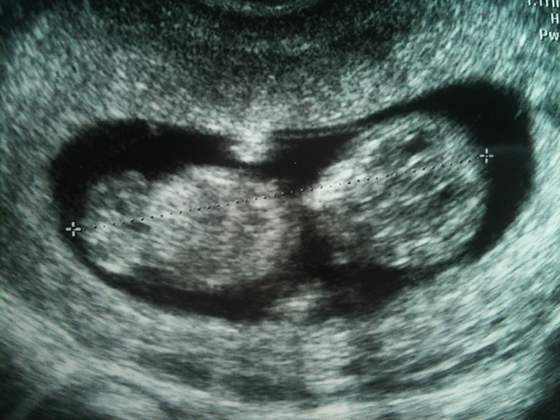

super!Ja już po badaniu, wszystko jest dobrze :-) dzidziuś ma 5 cm od głowy do pupy, wszystkie wymiary ok, ruszał się na boki i trzymał się łapkami za głowę, ryczałam jak głupia. Doktor pokazywał mi kolana, łokcie, pęcherz, żołądek itp. Następna wizyta za miesiąc, ale nie ma konieczności robienia usg, następne usg dopiero w 20 tygodniu ma być. Pozdrawiam Was w ten piękny dzieńnareszcie mogę się wszystkim pochwalić że jestem w ciąży!

Zobacz załącznik 437138